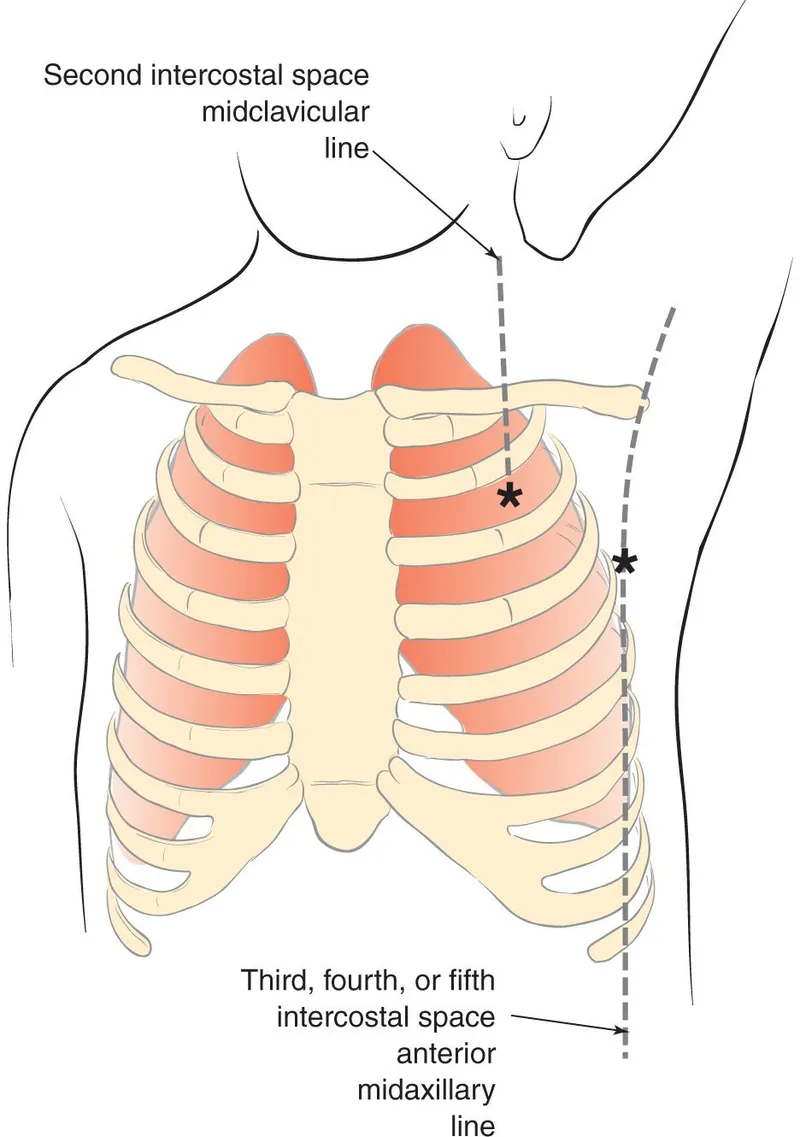

- Tension Pneumothorax: Hypotension, JVD, absent breath sounds, tracheal deviation. Immediate needle decompression (2nd ICS MCL or 5th ICS AAL) followed by chest tube.

- Immediate needle decompression (2nd ICS, MCL) → chest tube.

- Needle Decompression: 2nd ICS, mid-clavicular line.

- Tube Thoracostomy: 4th/5th ICS, anterior-axillary line.